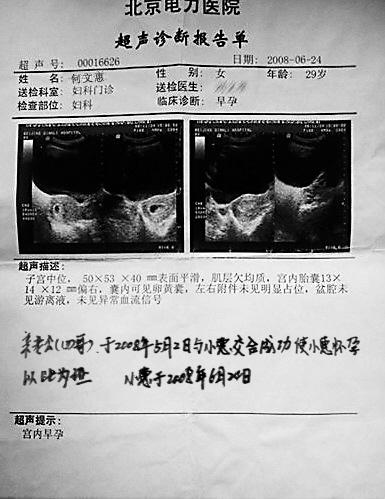

忽然想起來還有一個圖片呢,打開一看,是《超聲診斷報告》,上面赫然印

著老婆的名字和宮內早孕的診斷結果,上面還有老婆娟秀的字跡:「親老公(四

哥)於2008年5.1與小惠交合,成功使小惠懷孕,從此小惠就是四哥的人

了,以此為證。小惠於2008年6月24日。」

這是四哥發給我的我老婆的超聲波檢驗報告,以此為原創證據,別的壇子裡

發這篇文章沒有這個的。

圖片附件: [超声报告] csbgd.jpg (2011-11-14 11:05, 94.82 K)